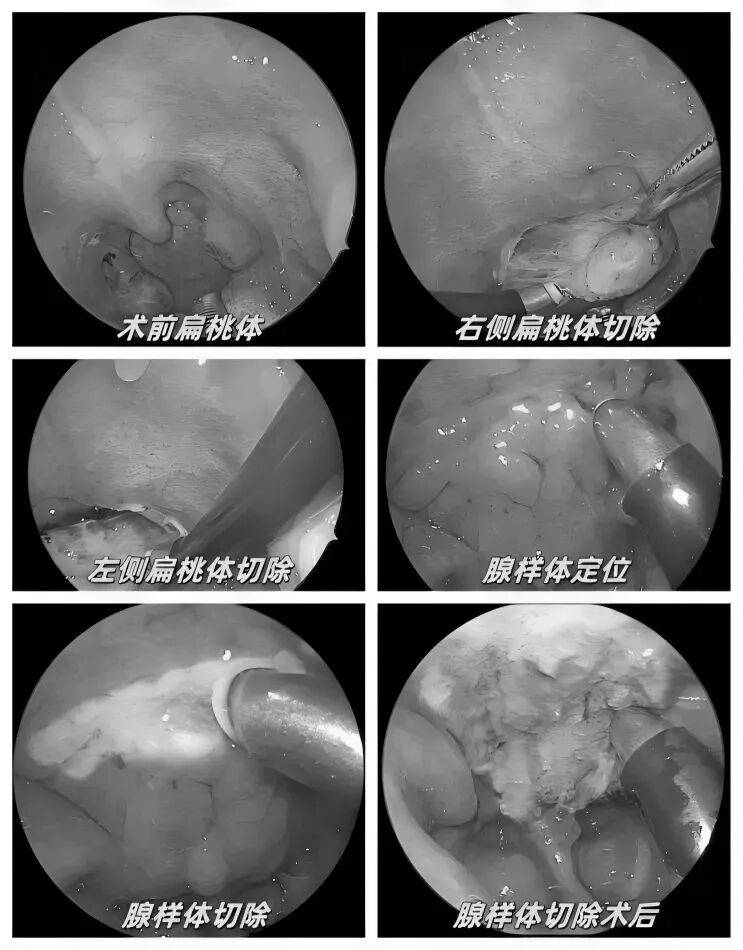

耳朵反复流脓、听力下降还有异味?当心,这可能是慢性化脓性中耳炎的症状。由于早期症状时好时坏,很多人觉得不是大问题,但拖延不治可能对听力造成不可逆的损伤。今天我们就来认清它的真面目,学会如何科学应对。 什么是“慢性化脓性中耳炎”? 慢性化脓性中耳炎,俗称“灌耳心”,典型症状包括耳内反复流脓(常为脓性分泌物,严重时可伴有臭味)、听力下降以及耳鸣等,部分患者还可能伴有眩晕。很多人是从小时候就开始出现症状,尤其是耳朵进水后容易急性发作或加重,成年后,听力持续减退往往成为主要困扰。 如果不及时治疗,炎症可能“向上”蔓延到颅内,引发脑膜炎、脑脓肿等危及生命的严重并发症。也可能侵犯面部神经或平衡器官,导致面瘫、持续眩晕或平衡障碍。最直接的后果是听力会不可逆地下降,严重时可能导致完全失聪。 “慢性化脓性中耳炎” 如何治疗? 慢性化脓性中耳炎的基础治疗需先用双氧水或生理盐水清洗耳道脓液,再滴入敏感抗生素耳液(如氧氟沙星滴耳液)。急性发作或重症时需口服或静脉注射抗生素并辅以抗炎药。若药物控制不佳或已有器质性病变,则需手术,包括乳突切除术清除病变组、鼓膜成形术修复穿孔鼓膜、听骨链重建术改善传音功能及胆脂瘤清除术清除胆脂等。 患者常见问题解答 问 手术后多久能恢复听力? 答 术后恢复情况与手术方式、个人身体情况有关。若为鼓膜修补手术,术后1—3个月左右,听力会逐渐改善,若进行听骨链重建手术,通常需要 3 到 6 个月,听力才能趋于稳定。术后需定期复查,监测听力恢复情况。 问 儿童患者能手术吗? 答 如果孩子的病情确实需要手术,家长不用太担心,儿童也是可以接受手术治疗的。医生会根据孩子的年龄大小、病情严重程度,选择最适合的手术方式,比如现在常用的微创技术,就能尽量减少手术对孩子耳朵的创伤,让孩子恢复的更好。 问 如何预防复发? 答 术后严格遵医嘱用药、复查,避免感冒及耳部进水,保持鼻腔通畅,减少咽鼓管阻塞。 贵州航天医院耳鼻咽喉科简介 张光进 中共党员,耳鼻咽喉科主任,副主任医师 临床擅长:对耳鼻喉头颈常见病的诊治具有丰富的临床经验,擅长鼻内镜、耳内镜、耳显微、头颈咽喉部肿瘤及眩晕手法复位等的诊疗。 曾先后前往第三军医大学西南医院、复旦大学耳鼻喉科医院、上海新华医院及北京友谊医院进修学习;遵义市医学会常务委员;主持及参与级科研课题2项,发表专业论文10余篇。 陈维信 九三学社社员,耳鼻咽喉科主任医师 临床擅长:对耳鼻咽喉科常见疾病的诊治具有丰富的临床经验,擅长耳、鼻、喉及头颈部位的手术。 曾先后前往上海交通大学附属仁济医院耳鼻喉-头颈外科、北京大学人民医院耳鼻喉-头颈外科参加鼻内镜外科进修学习。中国睡眠研究会委员,贵州省医学会耳鼻喉-头颈外科学分会委员,贵州省耳鼻喉-头颈外科学会理事,贵州省医学会变态反应学分会委员,贵州省防聋治聋技术指导组专家,遵义市耳鼻喉科分会副主任委员,遵义市医疗事故鉴定专家库成员;主持省部级科研课题2项,发表专业论文20余篇。 秦 晋 耳鼻咽喉科副主任医师 临床擅长:对耳鼻咽喉科常见疾病的诊治具有丰富的临床经验,擅长耳、鼻、喉及头颈部位的手术。 遵义市医学会常务委员;曾先后在第三军医大学西南医院、湖南湘雅鼻颅底培训班进修学习。 贵州航天医院耳鼻咽喉科简介 基本情况 贵州航天医院耳鼻咽喉科拥有一支经验丰富、技术精湛的医疗团队,共有医师9名,其中副高级以上专家5名,医学硕士2名,开放床位20张,拥有德国WOLF鼻窦内窥镜系统、日本奥林巴斯电子喉镜、奥林巴斯电子鼻咽镜、丹麦临床听力监测设备、声导抗仪、听觉诱发电位、耳声发射仪、美国杰西低温等离子治疗仪、杭州好克鼻窦内窥镜系统、鼻动力系统、耳显微镜、耳用电钻、微波治疗仪等设备。 专科特色 (一)耳部疾病 耳内镜下胆脂瘤切除术、III型鼓室成形术+人工听骨链重建术。 (二)鼻部疾病 内镜下鼻息肉切除术、鼻窦功能开放术。 (三)咽喉疾病 内镜下扁桃体、腺样体低温等离子切除术 (四)交叉学科 1.经鼻内镜下眶内肿瘤切除术 2.经鼻内镜下鼻腔泪囊吻合术 诊疗范围 (一)常见耳疾的诊断和治疗:中耳炎、耳聋、耳鸣等。通过各种耳科检查手段,如耳镜检查、听力测试和耳脑干听觉诱发电位检查等,准确诊断患者病情,制定个性化治疗方案。 (二)鼻炎、鼻窦炎、鼻出血等鼻科疾病的诊断和治疗:采用微创技术,如鼻内窥镜检查、低温等离子手术等,为患者提供有效的治疗方案。 (三)喉炎、声带息肉、声带白斑等喉科疾病的诊断和治疗:通过声带电子镜、喉镜等设备,准确判断患者的喉部病变,为患者提供精准的治疗方案。 (四)鼻眼、鼻颅底相关手术。